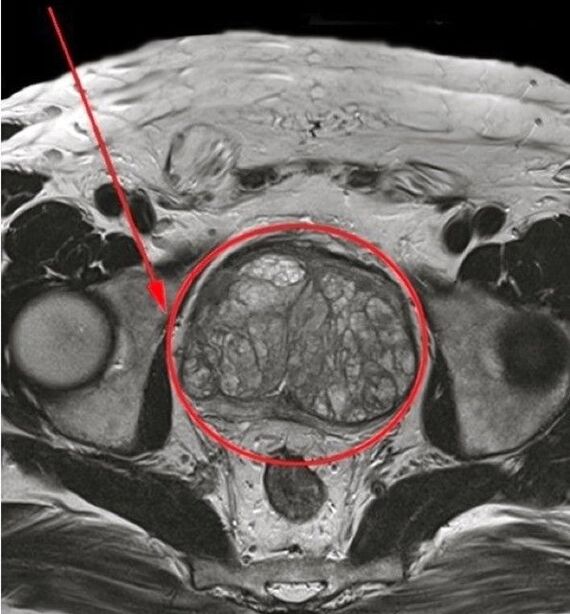

Ech hunn den Dokter gedréckt, d'Wichtegkeet vun der Zäitbehandlung verstoppt. Baséiert op de Resultater vun der Examen, ech war mat chronesche Prostatitis diagnostizéiert. De Spezialist recommandéiert datt ech e Cours vun der Behandlung mat engem natierlechen Medikament ënnergeet Predstonorm A Kapselen.